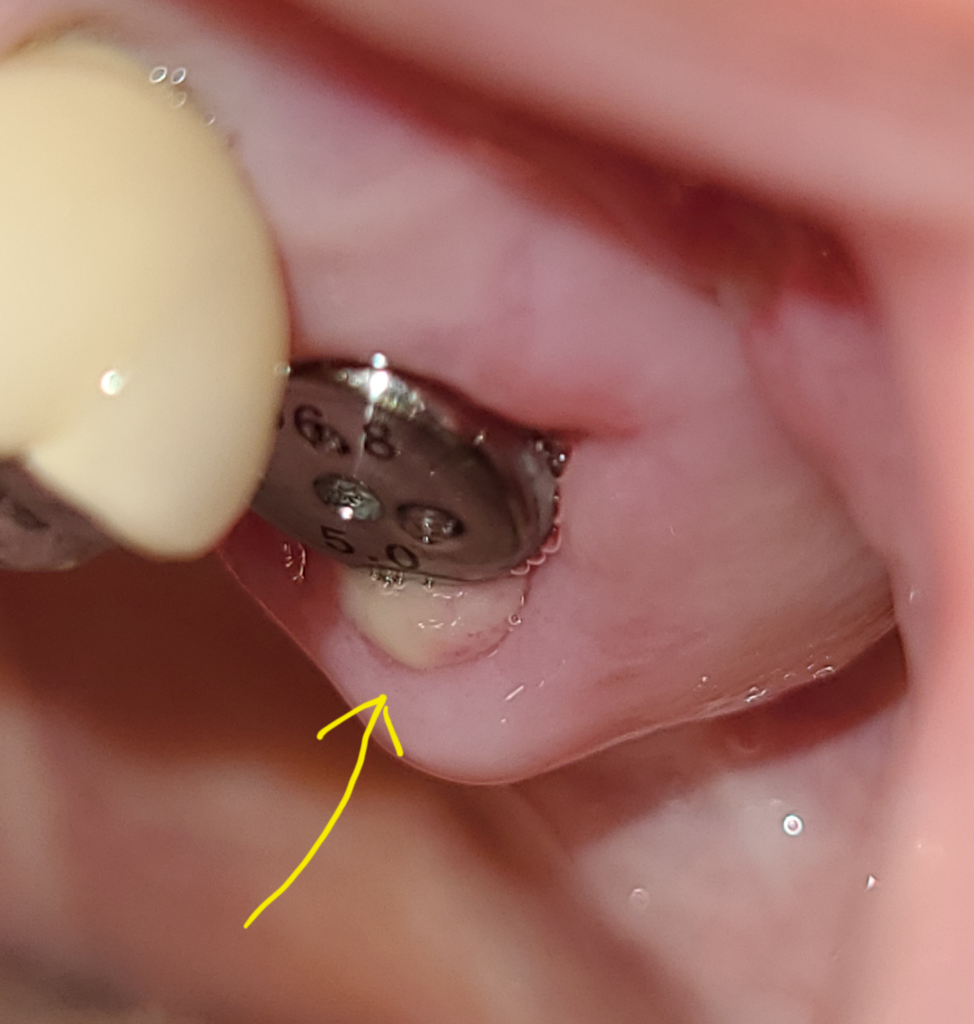

어금니에 염증이심하여 상악동까지 약간침범한상태였는데 발치하고 염증긁어내고 동시식립하였습니다

상악동에 약간걸쳐서 식립하였다고했습니다

8일째인데 이상한 조직이 살인지 염증인지 종양인지 모를것이 생겼고 이것이 지대주를 약간침범한상태입니다

저것이무엇입니까?

치은암은 아닌지 염증조직인지 정상조직인지요ㅠㅠ

지대주를약간덮었는데괜찮은건가요?

사진속 화살표부분입니다

정상적으로 아물고 있는 것입니다. 질문한 부위는 그 주변보다 아무는 속도가 늦고 붓기가 늦게 빠지니 다르게 보이는 것입니다.

염증을 긁어내고 나서 바로 심은신거라면 염증이 낫는과정에서 생길수 잇는 현상입니다. 문제가 잇는건 아니니 너무 걱정하지 마세요.